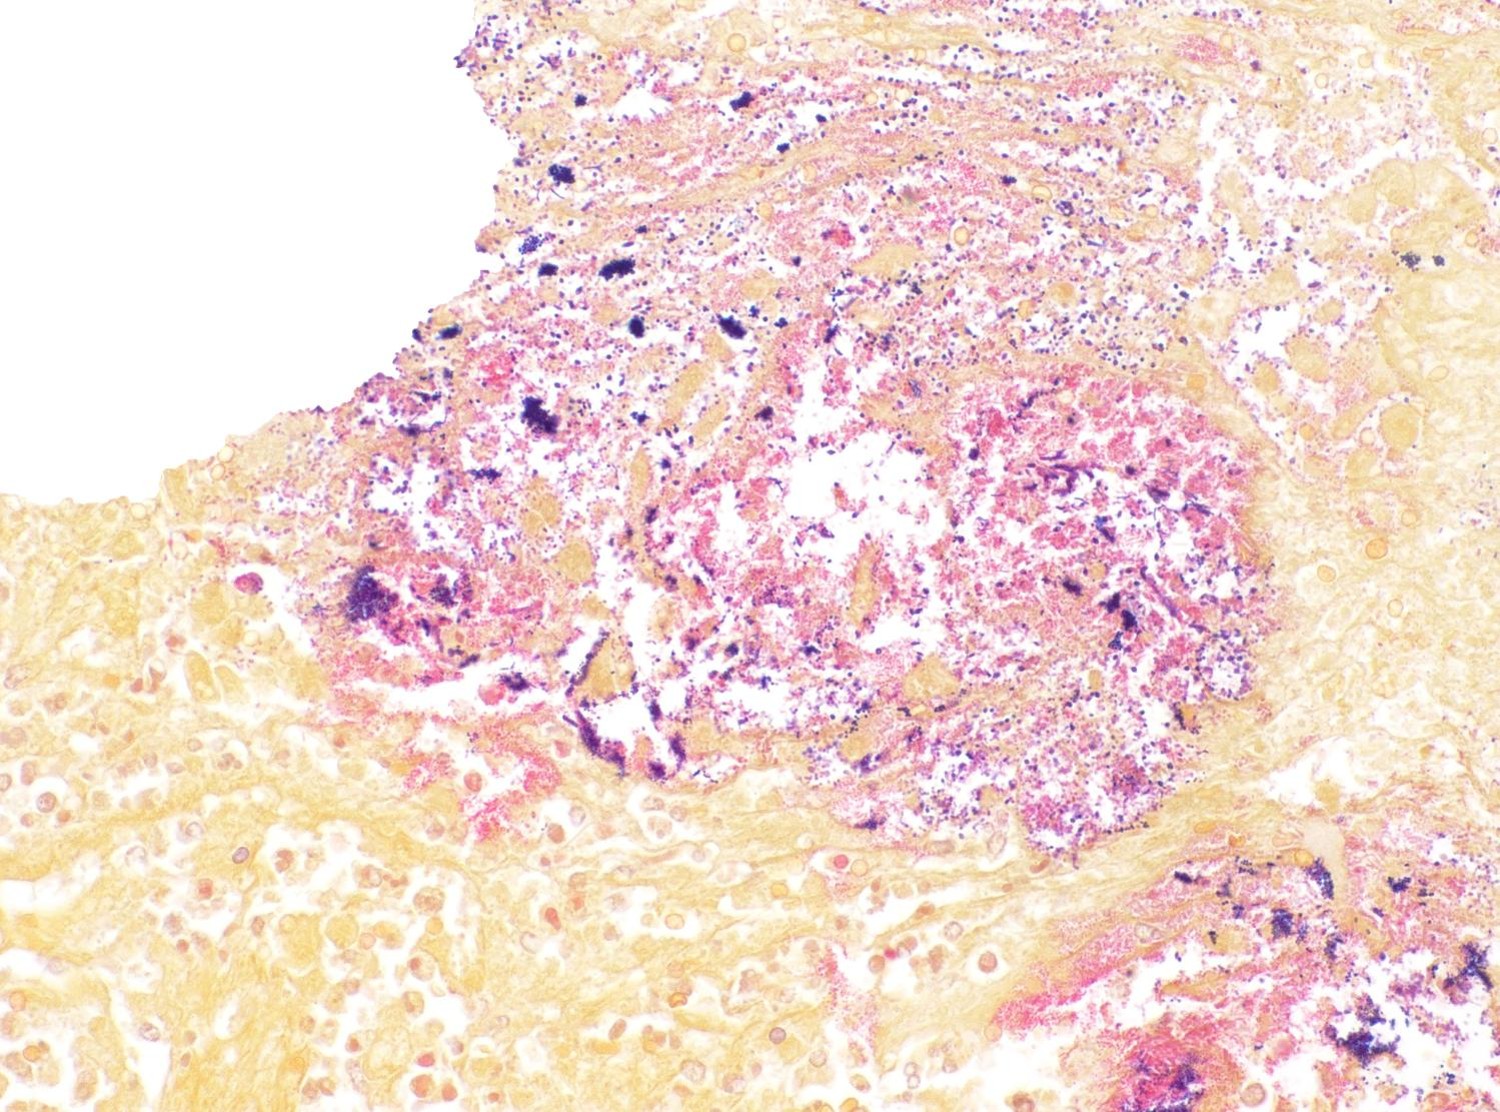

Colon: There is severe, diffuse necrosis of the mucosa where the superficial epithelium and, less prominently, the crypt epithelium is lost and/or show hypereosinophilia, pyknosis, karyorrhexis and karyolysis. The lamina propria is diffusely eosinophilic and infiltrated by a large number of viable and degenerated neutrophils and fewer neutrophils, plasma cells and macrophages; this cellular infiltration extends to the submucosa. Multifocally, the mucosa is covered by a thick pseudo membrane composed of fibrin, cell debris, red blood cells, neutrophils and myriad mixed bacteria. Several blood vessels of the lamina propria show thrombosis. In areas where the superficial epithelium is still present, erosions are seen through which large number of neutrophils are seen exiting the lamina propria into the lumen (volcano lesions). The submucosa is severely dilated and edematous; there is vascular congestion and the lymphatic vessels are dilated. The serosa shows reactive mesothelial cells.

Colitis, fibrinonecrotizing, diffuse, with thrombosis, volcano lesions, submucosal edema and mixed bacteria

Clostridioides difficile (renamed in 2016 from Clostridium difficile) affects many species of all ages.1,3 The primary clinical sign is profuse diarrhea. Histologically, “volcano lesions”, as seen in this case, are a hallmark of C. difficile in the acute phase of infection.3,4 Although other organisms (including Salmonella) can cause these lesions, they are considered classic for C. difficile. These lesions are characterized by micro-ulcerations of the mucosa with necrotic debris and neutrophils being “spat out” into the lumen, giving it the appearance of lava spewing from an erupting volcano. Following acute infection, volcano lesions become difficult to see histologically due to the progression to a full-blown necrotizing colitis, the lesions of which are non-specific and can be caused by a number of enteric pathogens (i.e. Salmonella spp, Brachyspira spp, etc.). As mentioned by the contributor, culture is a more suggestive method for confirming a diagnosis of C. difficile, but the results must be interpreted with caution as, according to Dr. Uzal, 3% of clinically normal horses will grow C. difficile on culture of enteric content.4